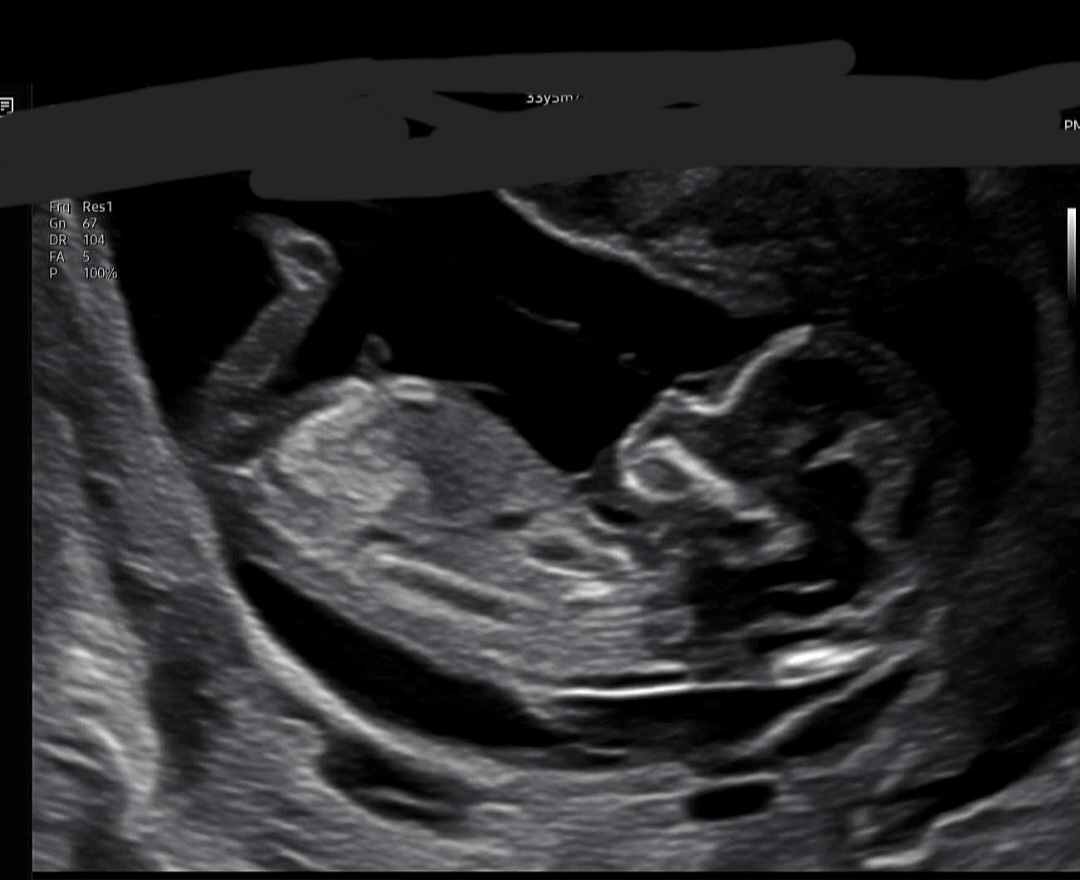

12주4일차 봐주세요♡♡

성별 도와주세요!